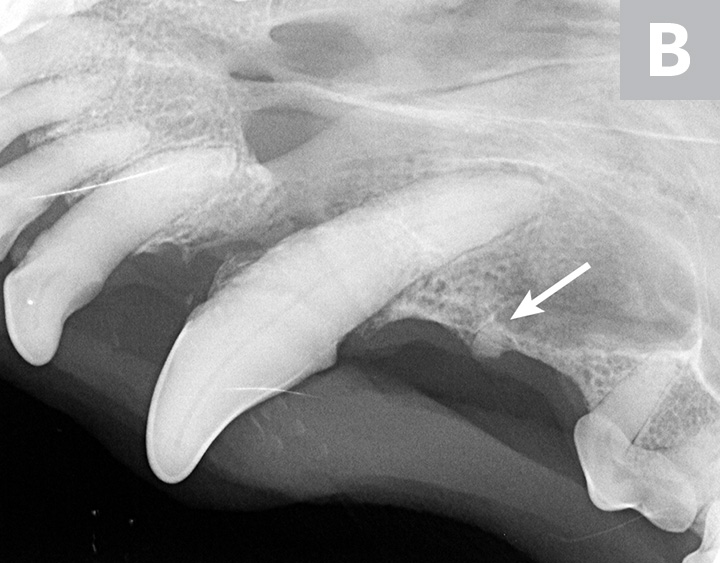

Three dental radiographs.

Figure 2

Dental radiographs of the right (A) and left (B) maxillary canine teeth (lateral views) and the rostral maxillae (C; occlusal view) confirmed mild horizontal and severe vertical bone loss at the mesial aspect of both maxillary canine teeth. Moderate to severe horizontal bone loss at the right maxillary first incisor tooth (blue arrow) and total loss of attachment with inflammatory root resorption at the right maxillary second incisor tooth (yellow arrow) were present. The remaining maxillary incisor teeth were affected by mild horizontal bone loss. Although the occlusal view of the rostral maxillae is slightly asymmetric, osteolysis was evident in the area of the left palatine fissure (red arrow). Mild horizontal bone loss was diagnosed at several other teeth. In addition, retained root tip of the left maxillary (presumably) first premolar tooth (white arrow) was identified.